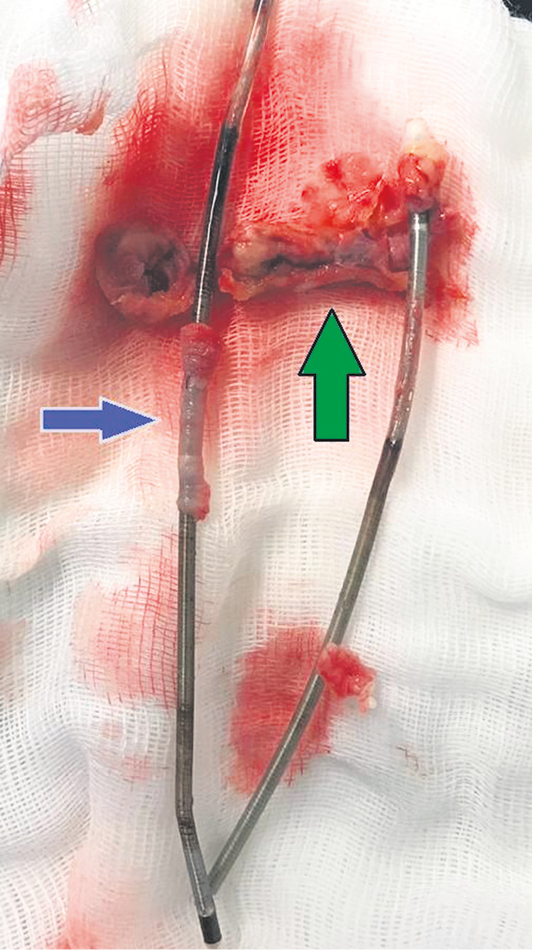

It was during this hospitalization, with the background of massive antibiotic therapy, that the oral cavity sanitation was urgently completed, and on May 07, 2019, 7.5 months after the onset of the disease, during an open surgical intervention, the system of constant electrocardiostimulation was completely removed and the heart chambers were sanitized while extracorporeal circulation and cold cardioplegia. On both electrodes, multiple vegetations were found, both ordinary — large formations on the “stem” fixed to the electrodes, and vegetation of the “sleeve” type (Fig. 4). During the surgical revision, vegetation was revealed on the anterior cusp of the TV, which necessitated partial resection and suture plasty of the anterior cusp of the TV. Fortunately, there were no indications for pacemaker reimplantation, since in the preoperative period it turned out that the patient was predominantly in sinus rhythm, there were no signs of AV block (both subtotal and complete). The early postoperative period was complicated by two episodes of ventricular tachycardia on the 2nd and 4th days after surgery with outcome in ventricular fibrillation and sudden death. Resuscitation measures were successful.

Fig. 4. Postoperative photography: fragments of removed electrodes. There are two types of vegetation fixed on electrodes: classic giant vegetation, reaching a length of 5.5 cm (green arrow); vegetation, braiding the electrode like a “sleeve” or “stocking” (blue arrow).

On 10.10.2019, 11 months after the onset of the disease, the pacemaker endocardial system was extracted, and the permanent pacemaker was reimplanted into the epicardial position under artificial circulation. Intraoperatively, the presence of massive vegetation of ‘sleeve’ type on the electrodes was confirmed (Fig. 7), and vegetation on the TV was also detected, which required its removal and plastic surgery of the TV according to De Vega.

Fig. 7. Intraoperative photographs. Massive vegetation of the “sleeve” type on intracardiac fragments of the electrodes (blue arrows).